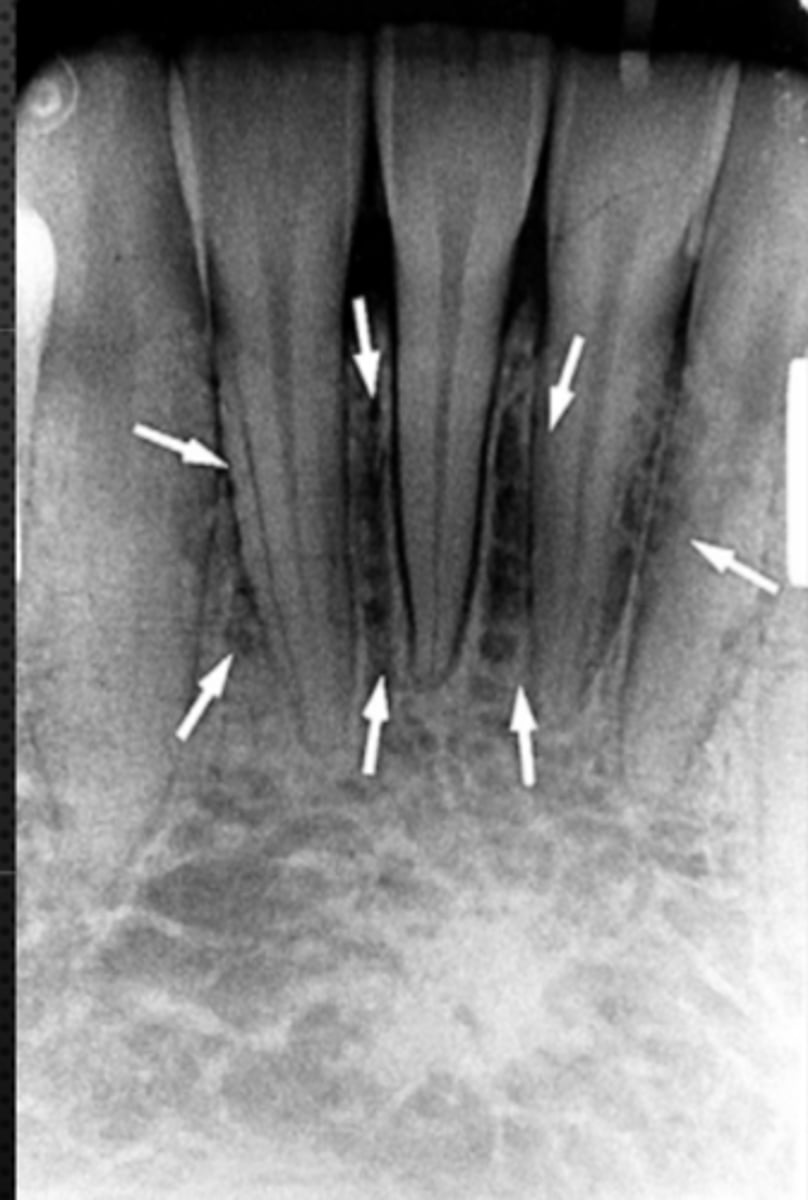

Nutrient canals (neurovascular canals)

Identify the radiolucent structure

<p>Identify the radiolucent structure</p>